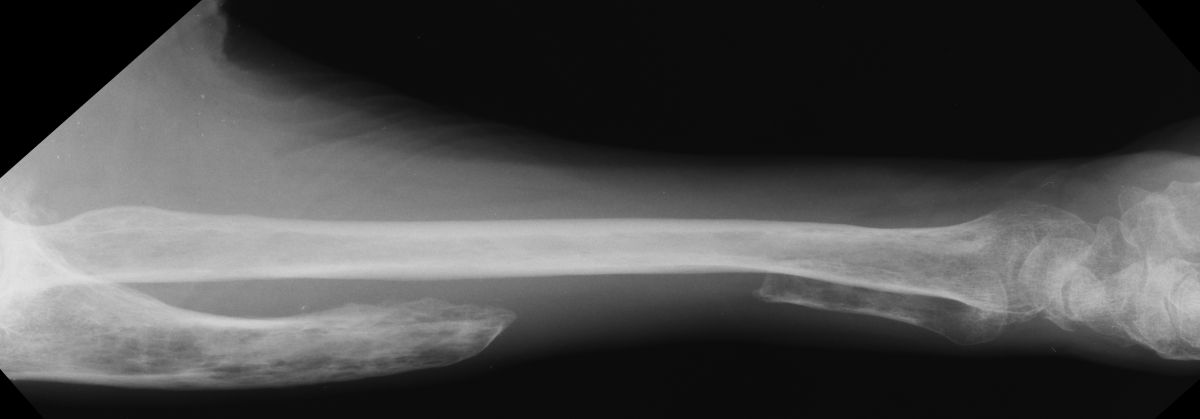

| Case 2. This 74 year old man presented with elbow pain years after wide excision of the central ulna and forearm radiation for a malignant tumor. The abnormal load on the radiocapitellar joint has resulted in degenerative changes. |